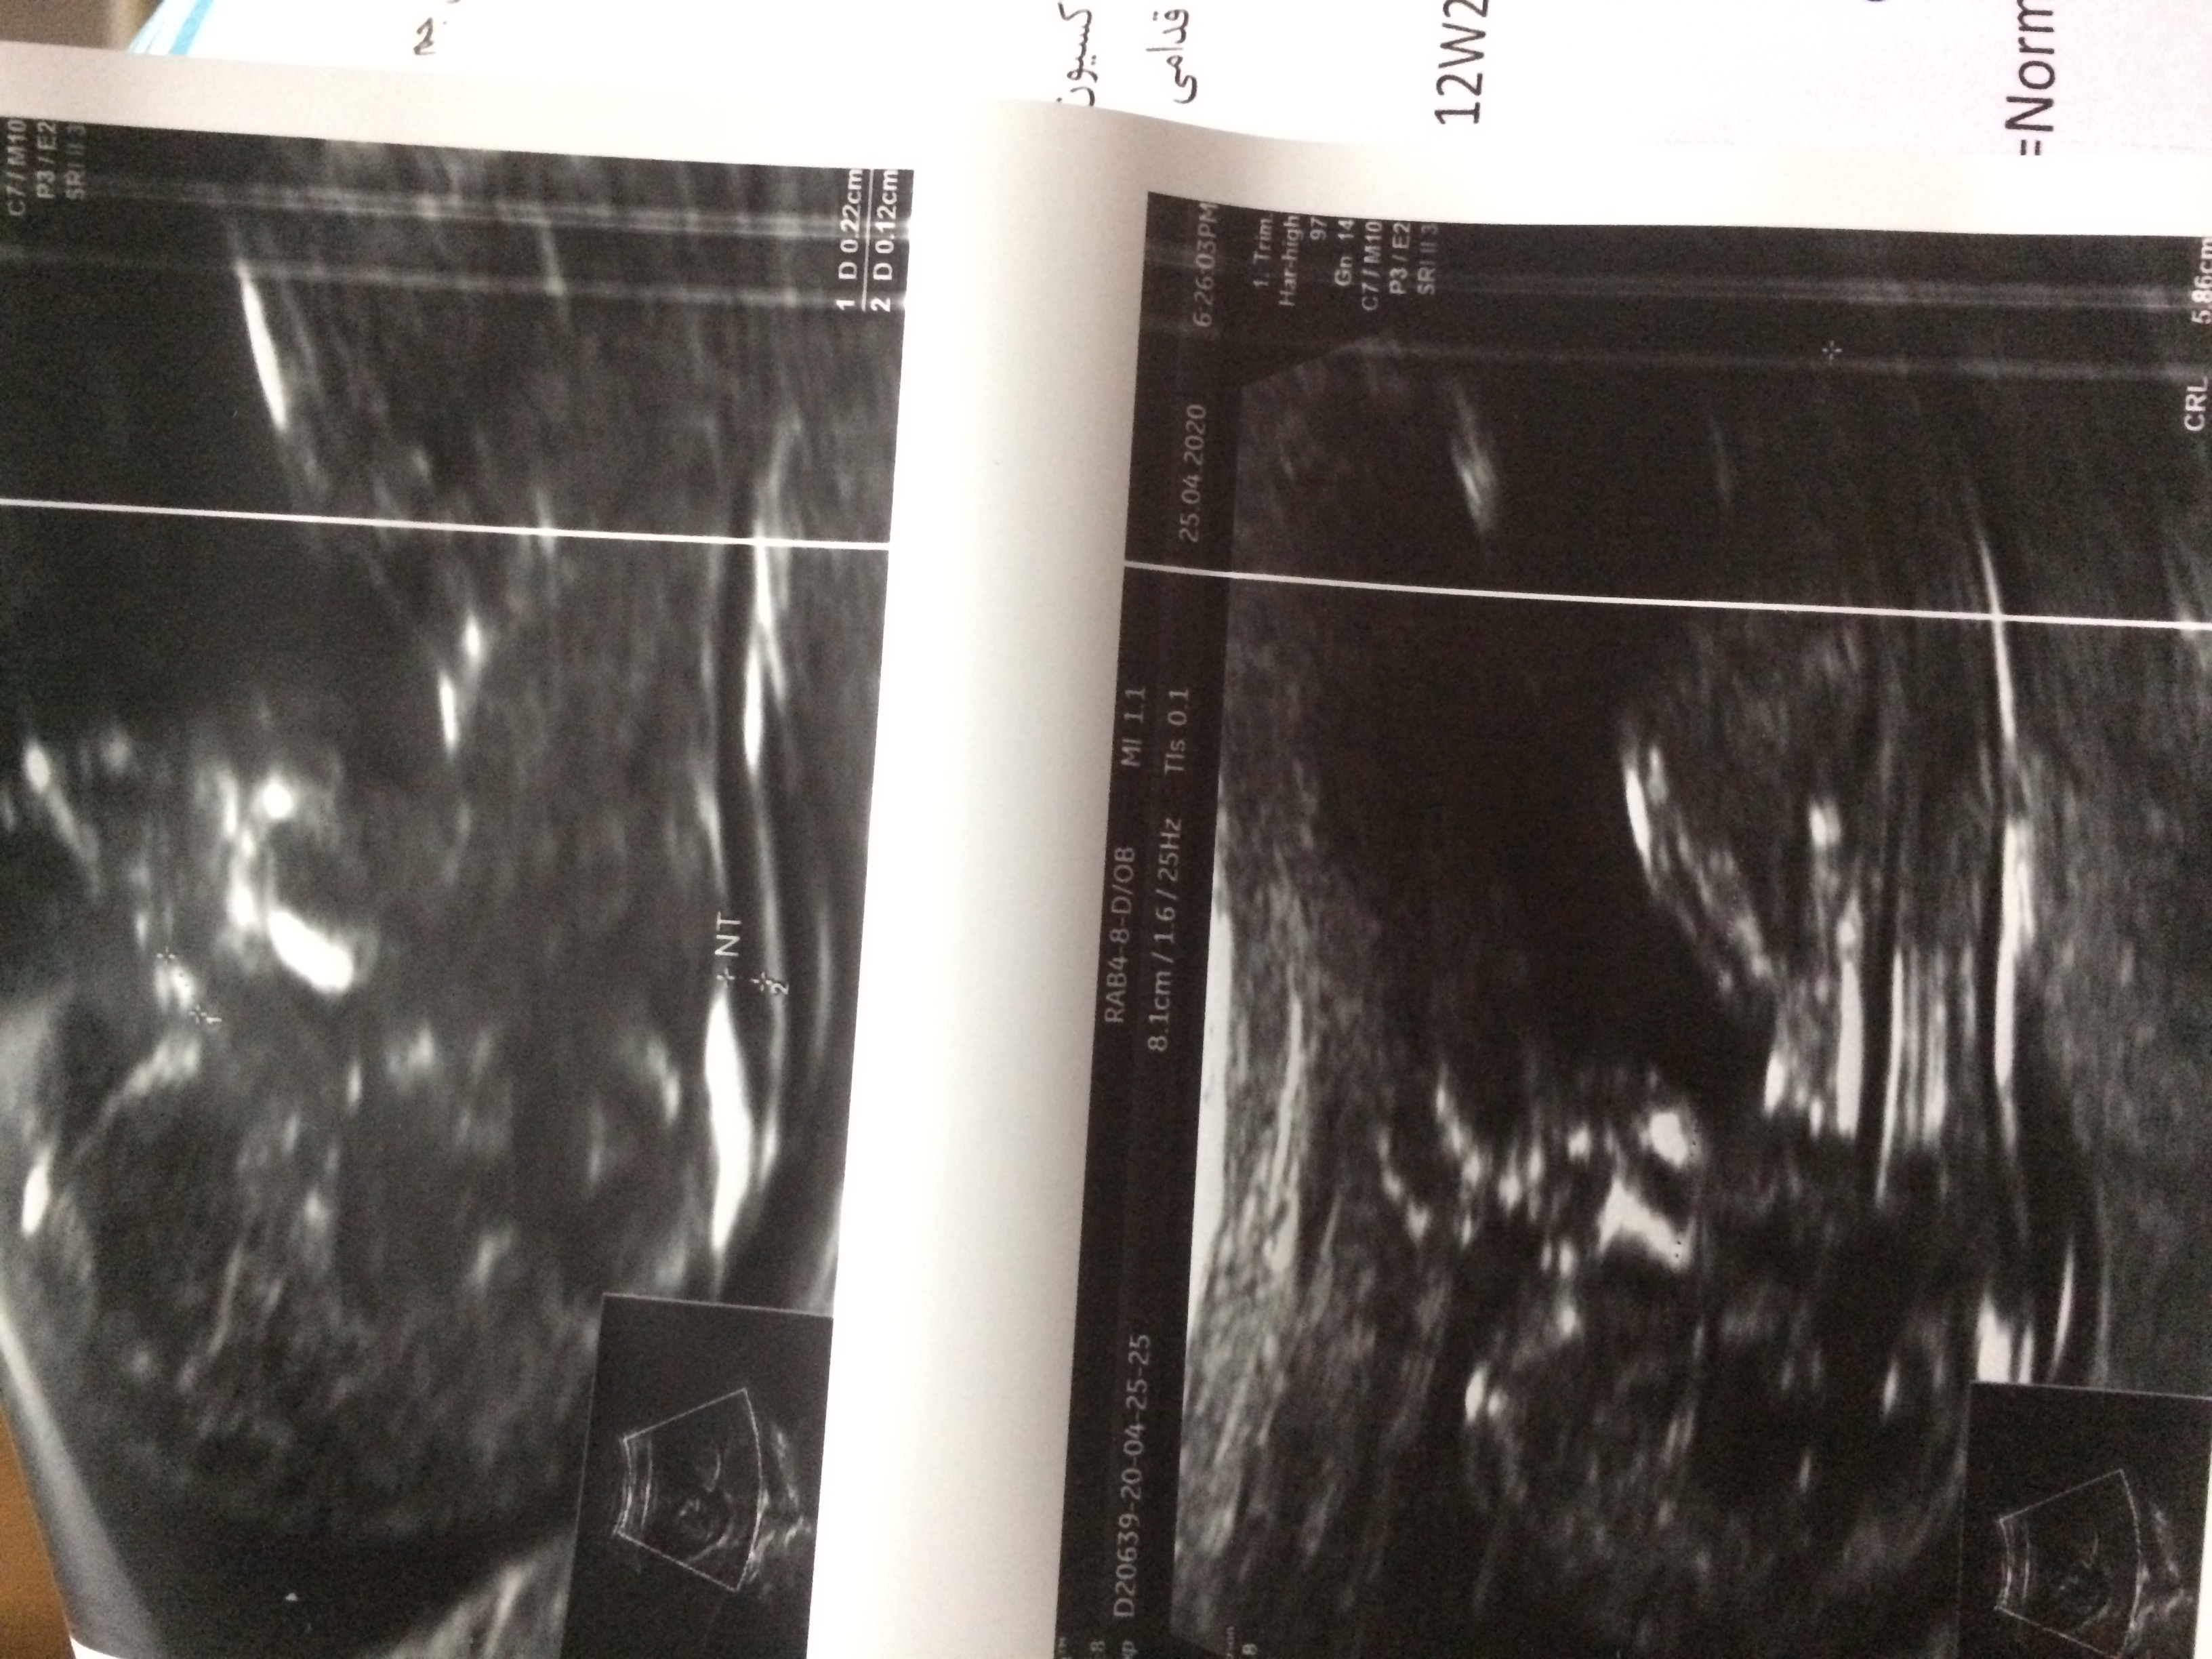

بیاین سونو ان اتی منو ببینید

عزیزم همه چی خوبه فقط هماتوم داری بیشتر رعایت کن و کارای سنگین نکن و اگه دکتر شیاف داد استفاده کن

اره برا هماتومم شیاف میزارم

استراحت مطلق فعلا حتی سرپا هم زیاد واینستا... زیر جفت خونریزی کرده زیاد تحرک داشته باشی ممکنه جفت کنده بشه... فقط دراز بکش مایعات... شیاف سیکلوژست 400 اگه دکترت صلاح میدونه و استرس هم نداشته باش

نمیدونم عزیزم هرچی که هست سلامت باشه فقط مواظب باش رابطه هم فعلا نداشته باش